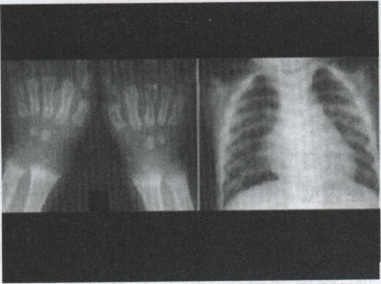

28.男,3岁,腕部变形,胸廓畸形,应诊断为()